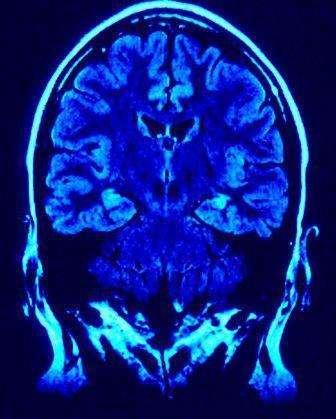

As a result, in order for an injured player or his family to obtain money from this fund, determinations as to the "severity" of the brain injuries will have to be evaluated by "independent doctors working with settlement administrators appointed by the District Court." Of course, this begs the question, what about the players who are only determined to have mild traumatic brain injuries? Where is the line going to be drawn determining the degree of injury for these players?